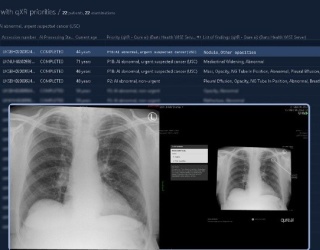

On the AI Marketplace stage, companies presented their AI solutions in short, memorable pitches. One focus was on applications for lung cancer screening, but also for chest and skull CT scans and fracture detection.

The scientific program was accompanied by a broad-based industry exhibition presenting the latest developments in AI analysis, structured diagnosis, workflow optimization, and digital patient management. Many visitors took the opportunity to try out technologies and talk directly to development teams.